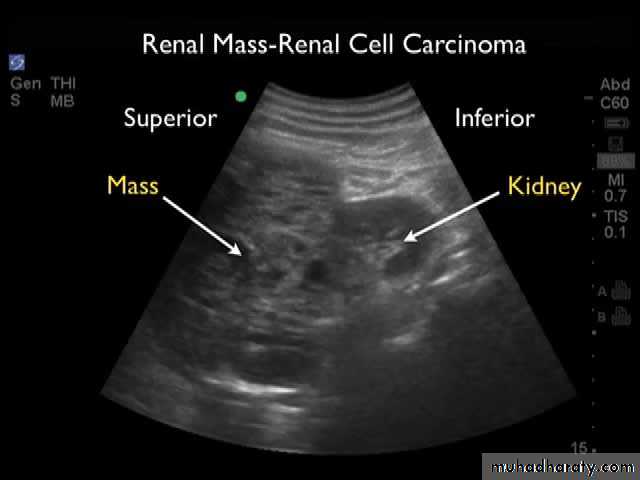

Renal cell ca destruction & missing of the normal appearance of the RT PCS

Left sided RENAL CELL CA large heterogeneous necrotic mass lesion